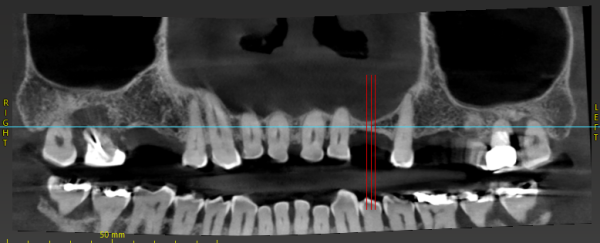

Implant treatment planning for #3,4,11,13,14

Hi everyone, got some questions for y’all experts.

The patient is my father in law, who has given me freedom to do all that I recommend except he really doesnt want to extract 1,2,15,16.

After studying the CBCT, I have some thoughts for these following sites, please help me double check and see if my thought process is correct.

Thank you all…